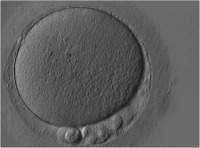

Die Bedeutung der Morphologie der Oozyte hinsichtlich ihres weiteren Entwicklungspotentials

Journal für Reproduktionsmedizin und Endokrinologie - Journal of Reproductive Medicine and Endocrinology 2006; 3 (1): 17-23 Volltext (PDF) Summary Abbildungen